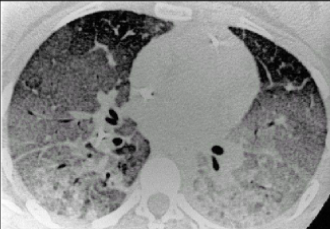

張新民介紹,在初步臨床研究的基礎上,治療結果表明,干細胞治療新冠肺炎患者安全有效,可以快速緩解或停止加重重癥和危重癥患者的呼吸困難。臨床表現、呼吸功能、影像學等方面均有改善,一般 8 - 10 天達到治愈水平。此外,干細胞在阻斷肺纖維化過程和促進肺損傷修復方面的作用表明,干細胞對預防肺纖維化和改善新冠肺炎患者的長期預后具有獨特的優勢。

急性呼吸窘迫綜合征( ARDS )是一種嚴重的免疫性和炎癥性疾病,其特征是肺部廣泛炎癥。它是一種臨床綜合征,其特征是由多種病因引起的呼吸窘迫、低氧血癥、彌漫性肺浸潤和呼吸衰竭的快速進展。目前,缺乏有效的藥物治療。